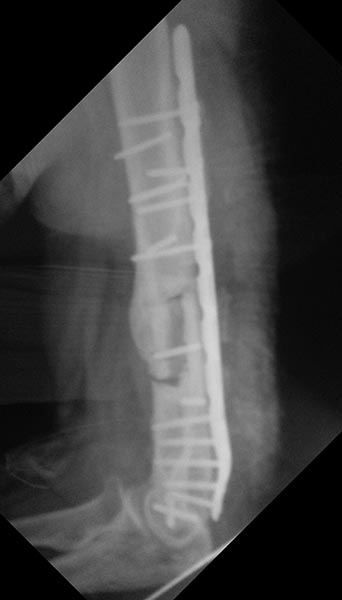

Уважаемые коллеги, хотелось бы услышать вашего мнения по поводу непростого случая несросшегося перелома плечевой кости. Пациент 44года в 2013г закрытый многооскольчатый перелом дистального отдела правой плечевой кости. Остеосинтез пластинами в одной из столичных клиник. В п/о периоде нейропатия лучевого и локтевого нервов, за 10 месяцев лучевой полностью восстановился, локтевой почти - небольшие парастезии в мизинце остались. Обратился ко мне летом 2015г (по совету общего знакомого), до этого обращался в учереждение где был выполнен остеосинтез, но в силу ряда причин не пожелал там оперироваться (кстати предлагалось только удаление металлофиксаторов). Пациент без вредных привычек (разве что переедание), из сопутствующей патологии ожирение (вес 160 кг рост 190см), сахарный диабет (невысокие цифры).В августе 2015г удаление металлофиксаторов, невролиз лучевого нерва, реостеосинтез (той же) пластиной, но в положеном задне-латеральном положении. При операции удалено около 50 куб. металлоза, при ревизии в месте несращения были подозрительные творожистые включения, но кость выглядела здоровой,все многократно промывал антисептиками, иссечены рубцы, края отломков адаптированы друг к другу по типу замка - зона контакта большая, суммарно кость укорочена около 1,5 см. Перед операцией планировал ставить 2 пластину медиально, но до операции консультировался с более опытными коллегами и ставить вторую пластину не рекомендовали, все же заказал, но не поставил... операция заняла в целом 7,5 часов то ли устал, то ли действительно фиксация показалась достаточной учитывая характер сопоставления отломков (ну не суть важно что сделано то сделано). Был установлен дренаж, но наследующий день он забился - удалил, опасаясь инфицирования довольно агрессивно промывал хлоргексидином, на 5 сутки на коже нижней трети плеча по наружной поверхности появился пузырь 10 на 10 см, промывать перестал. Рана зажила первичным натяжением. Дефект кожи после фликтены постепенно заживает (от пересадки кожи пациент отказался). После операции нейропатия лучевого нерва (целостность сомнению не подвергается был выделен весь) за 2 месяца значительная положительная динамика. Иммобилизирован на косынке. В сентябре ниже локтевого отростка появилась небольная безболезненная припухлость по ходу рубца, была вскрыта и получен гной (со слов коллеги я был в отпуске), через 4 дня я видел рану гноя не было отделяемое серозное больше похоже на синовиальную жидкость (предполагаю что идет от локтевого отростка к которому было пришито сухожилие трицепса тисорбом они часто текут по личныим наблюдениям, но не факт...), неоднократно посев роста нет, кровь спокойная, температуре нет соответственно. 2 месяца после операции (22.09.15г) КТ контроль - все стабильно. Две недели назад разрешил иногда снимать косынку но рукой не пользоваться. Неделю назад пациент стал говорить что появился хрукт. Рентген контроль - перелом 2х винтов нестабильность вторичное смещение. Предварительно планирую брать на ревизию удалить винты с проксимального отдела, репозиция остеосинтез и дополнительно медиальная реконструктивная? пластина.

1. По представленной информации не совсем понятен смысл выполненной вами в августе операции. На передне-задней рентгенограмме убедительных признаков несращения нет. Было бы неплохо выложить вторую проекцию - возможно она действительно продемонстрирует несращение. Прикрепленная КТ не читаема (и наверное это КТ за сентябрь). (Кстати желательно уменьшить размер файлов согласно инструкции на сайте - очень долго грузятся).

Пока же кроме варусной деформации, нескольких сломанных винтов и костных наростов (которые можно трактовать как признаки инфекции) на прямом снимке ничего страшного не видно. Такая деформации клинически вряд ли будет играть роль у пациента весом 160 кг.

Может не так хорошо видно, но ВСЕ винты были сломаны и из 7,5 часов 5 ушло на удаление и невролиз, может не так хорошо видно но ВСЕ винты были сломаны, все было в грубом рубцовом конгломерате и металлозе, промывал хлоргекс и бетадином, фликтеной назвал условно потому как предполагаю что из-за выраженного отека и плюс дополнительно накачивал промывая остро появился пузырь отслоивший кожу (как его по другому назвать не знаю), насчет зачем полез, да почему то многие считают что пациенту нужно было ждать пока не сломается пластина, компрессию дал, между фрагментами винт поставил на снимке видно(хотя думаю не стоило он и сломался). И снимок за 6 месяцев до последнего где было только 2 винта сломано выкладываю.

Повторно планирую ставить эту же пластину как минимум из тех соображений что бы не удалять винты из дистального отломка и максимально сократить время операции, к тому же пластина хороша, кто не заметил это заднелатеральная синтезовская пластина, которая на мой взгляд оптимальна здесь поэтому и не стал другие ставить.

Угадать эту пластину по первичным снимкам сложно - как-то она не в ту сторону загнута. Я даже подумал было о пластине для наружного мыщелка большеберцовой кости:)